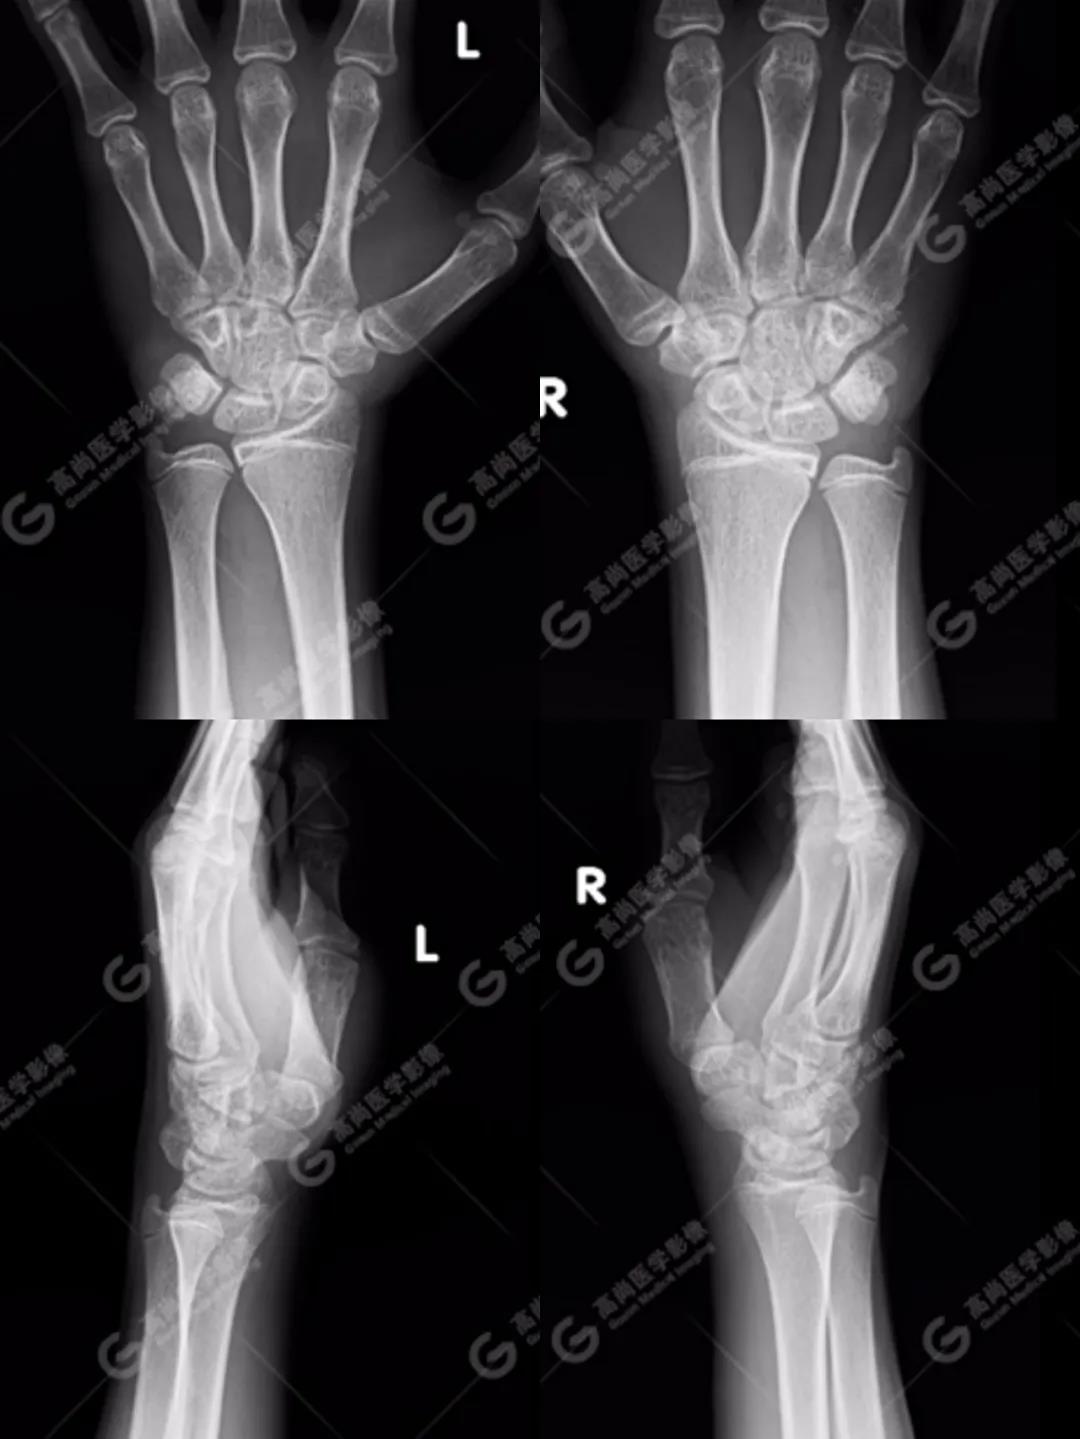

1、雙腕關(guān)節(jié)正側(cè)位平片

按照臨床診療的常規(guī)思路,遇到這種情況首先行X線平片攝影檢查(老百姓通俗講的“照片”)。

如下圖所見:雙腕關(guān)節(jié)諸骨未見明顯骨折征象。

沒有看到明顯的骨折線,患者的疼痛是不是軟組織損傷造成的、回家擦一些紅花油之類的外用藥就ok了的“小問題”呢?考慮到孩子即將面臨考試,家長還是不放心,擔心X線影像重疊等因素造成漏診,想進一步明確,提出進行CT檢查(由于成像原理的差別,CT對于細微骨折的顯示要明顯優(yōu)于常規(guī)X線攝影)。